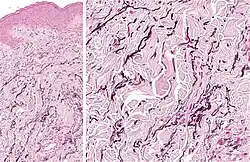

| Elastosis perforans serpiginosa | Degenerated elastic fibers and transepidermal perforating canals (arrow in image points at one of them)[18] |

|